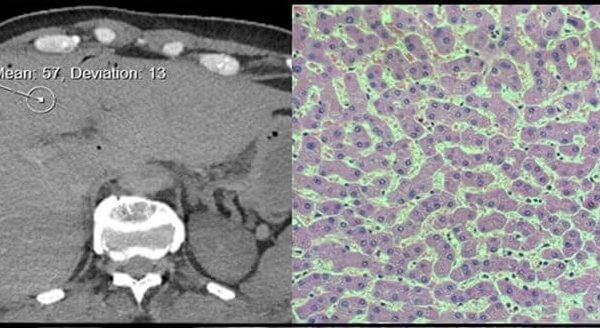

Pathology